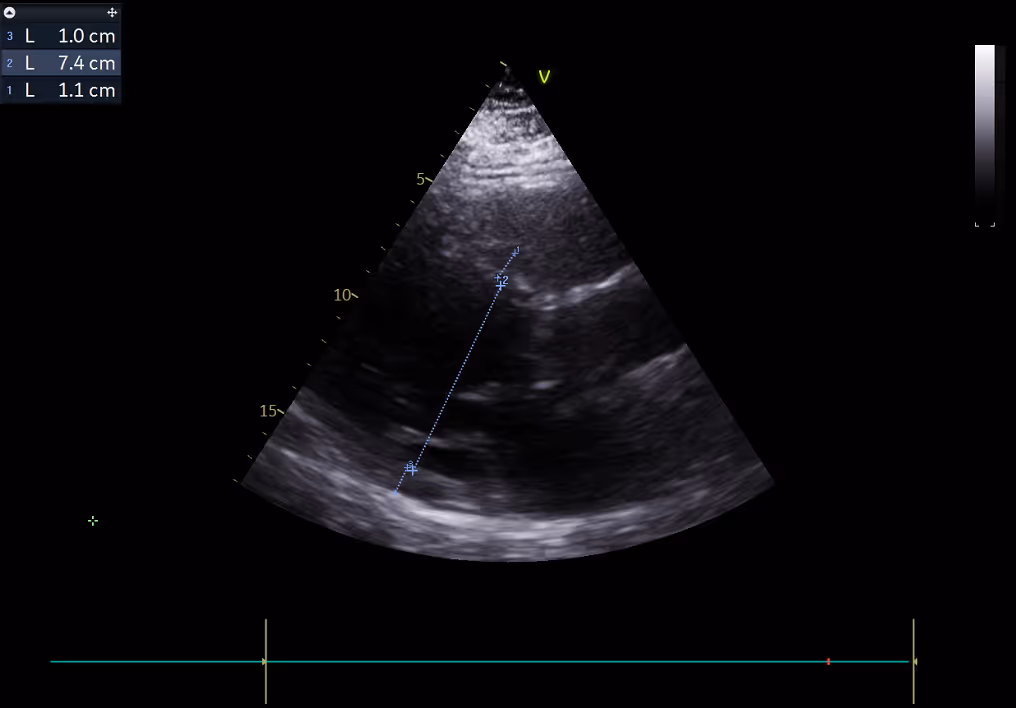

Echocardiography on admission documented a dilated left ventricle (EF 45-50%), aortic regurgitation ¾, moderate aortic stenosis (gradient 43/29 mmHg), masses on aortic valve (Image 2-3, Video 1-3).

Image 2: Echo on admission, dilated left ventricle